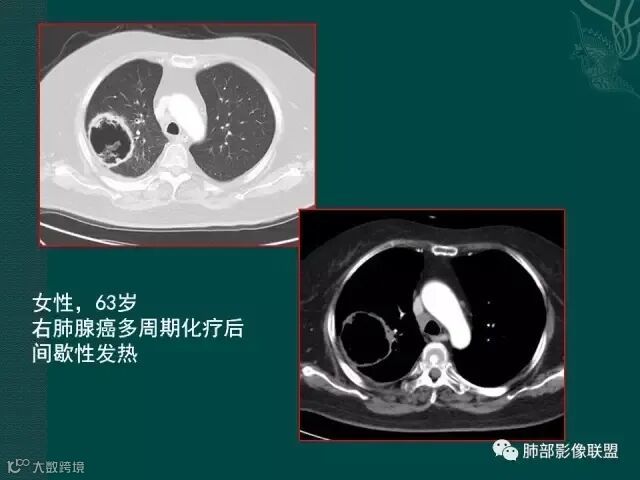

上一个是磨玻璃密度肺癌,边缘清晰,内有分隔,空洞型肺癌伴磨玻璃密度影的,100%为腺癌,很显然这是个假性空洞;

下一个也是肺癌,内有分隔,外下缘箭头所示也是磨玻璃影,这也是腺癌,同时可见叶间裂有转移灶。